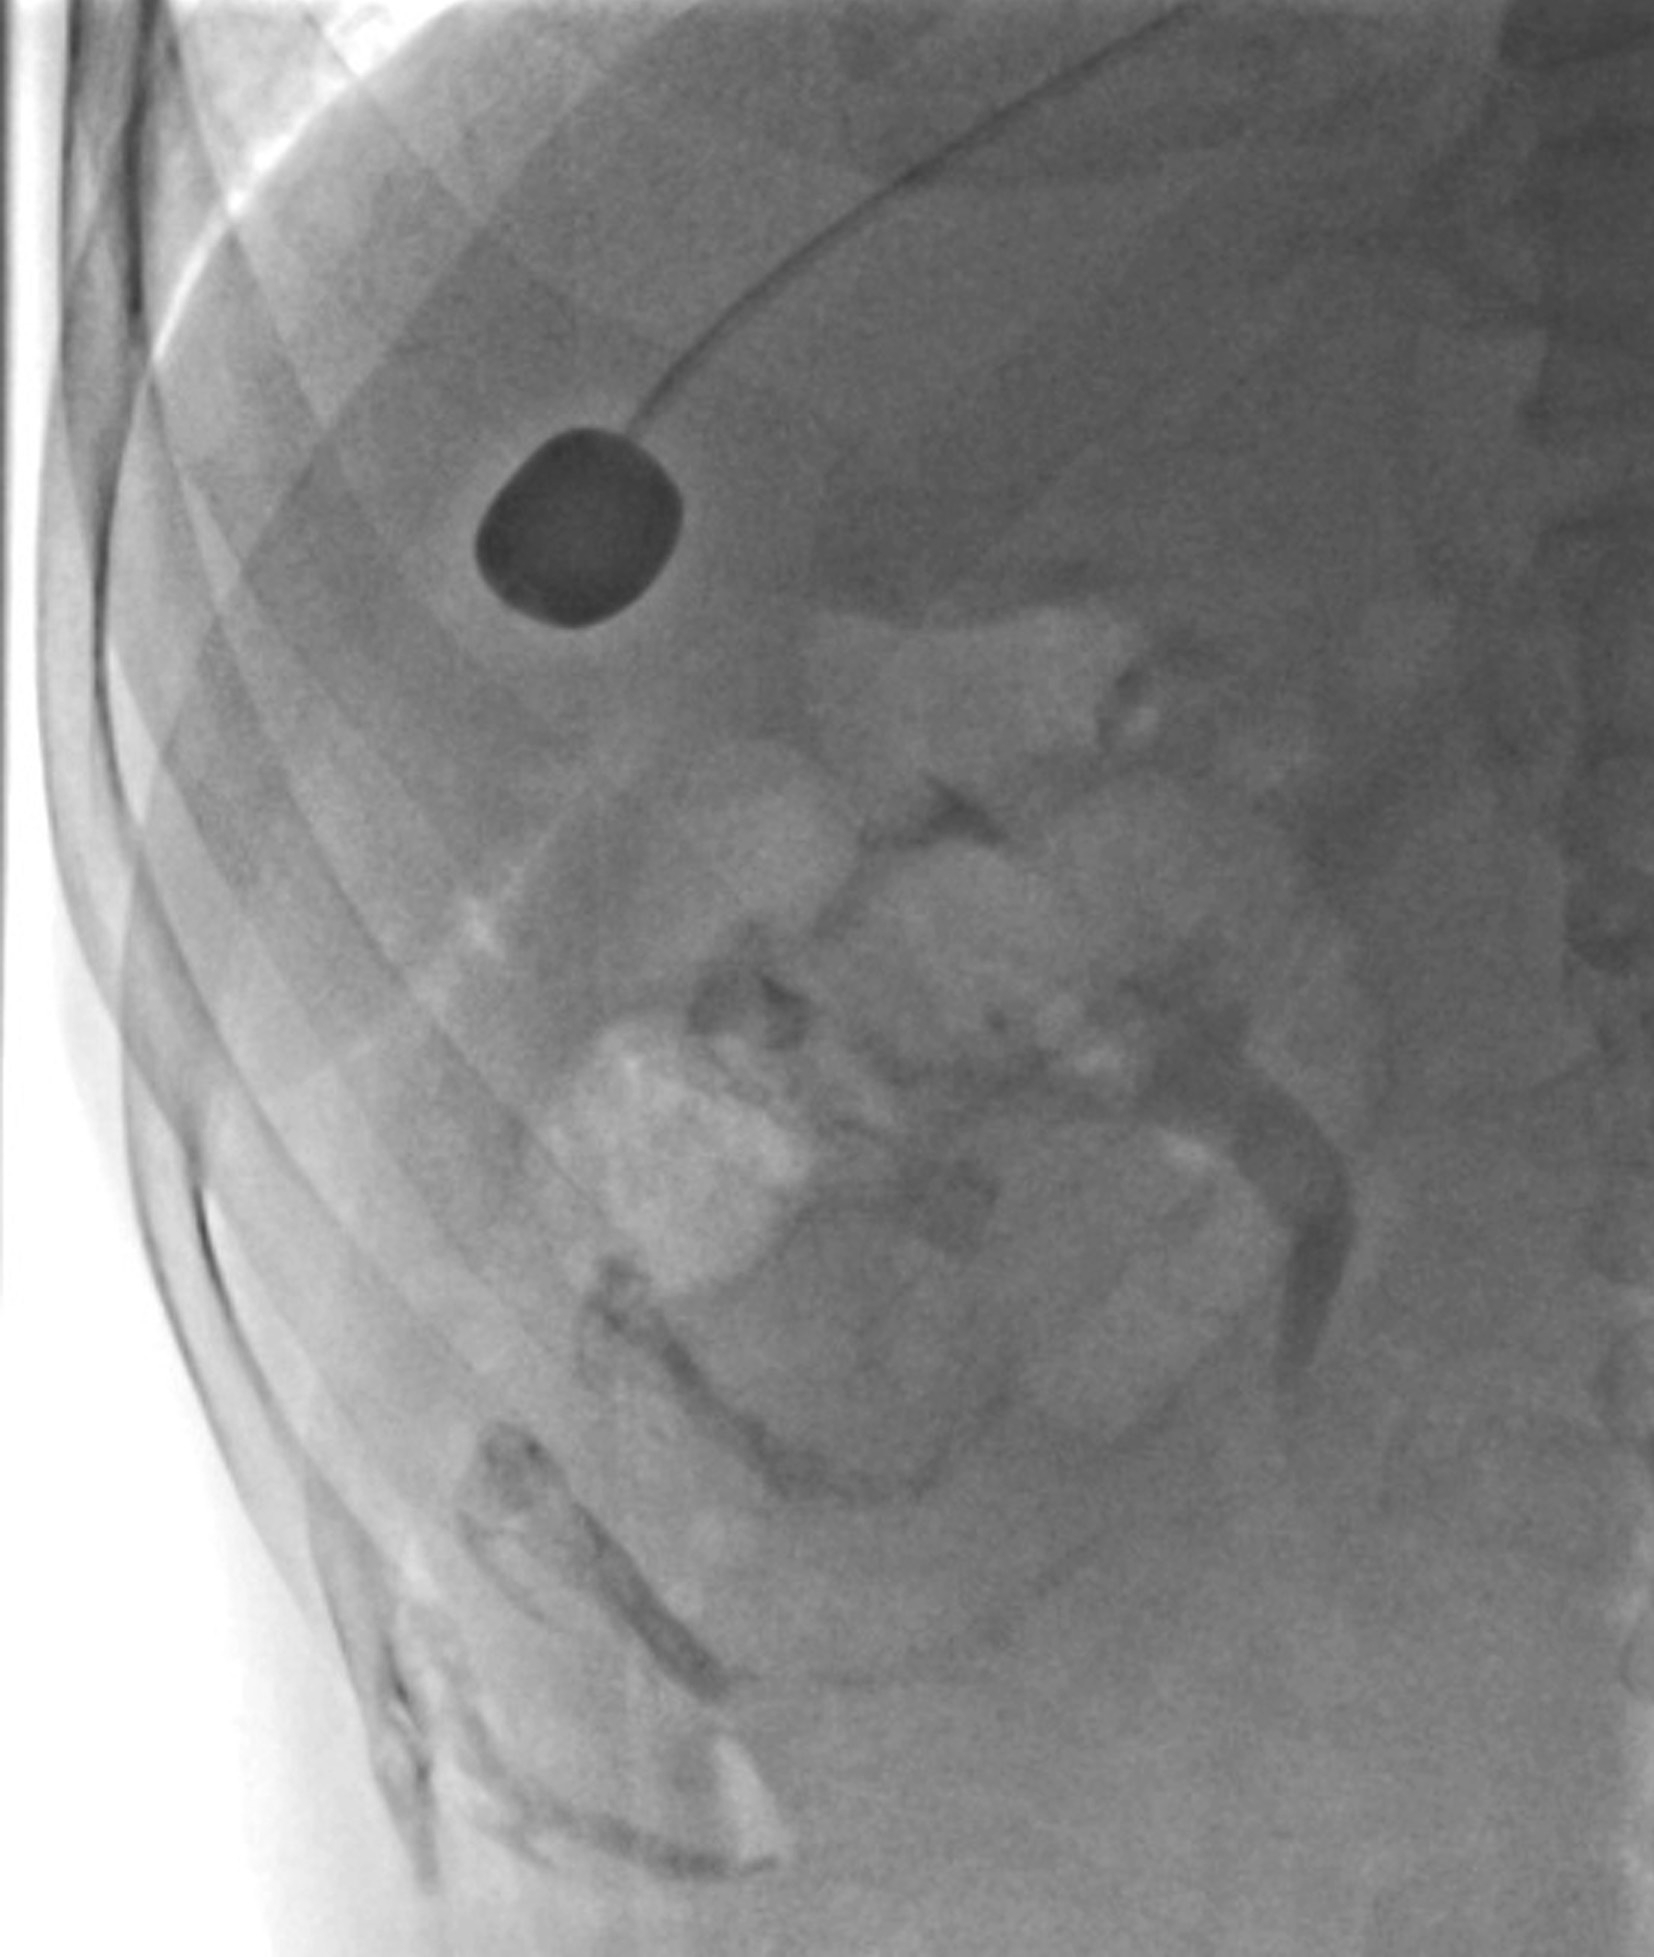

目的在于进一步了解肿大肝脏对胃、十二指肠和结肠肝曲的压迫和移位情况。肝癌患者常伴发肝硬化,应行钡餐检查除外食管、胃底静脉曲张,以及阻塞性黄疸与胃肠道的关系等。

检查前准备:行胃肠道钡餐患者常规均应检查前禁食和禁水6h以上,检查前3天不服用含铁、铋、钙等不透X线元素的药物,以免残留在肠道内影响观察。常规采用钡剂检查(图5-21-33B、图5-21-33C),如有新鲜消化道出血患者禁行钡剂检查,必要时可行泛影葡胺等碘水检查。

图5-21-33 胃肠道钡剂检查图片

A.正常上腹部仰卧前后位,可见胃及肠管内少量积气;B.正常食管充盈像;C.正常站立位胃充盈像。

常规腹部平片对肝硬化诊断价值非常有限,但胃肠道钡餐检查可显示中晚期肝硬化患者食管、胃底蚯蚓状扩张的静脉。食管静脉曲张是门静脉高压的重要并发症,最主要见于肝硬化、门脉系统的血栓形成及上腔静脉综合征。

上消化道钡餐检查可见食管及胃底多发串珠状或蚯蚓状充盈缺损,食管腔轻度扩张,管壁蠕动减弱,病变常始于食管下段,后延及食管中段及胃底,极少数可波及食管上段。按静脉曲张的范围、程度及食管蠕动功能分为轻度、中度、重度。①轻度:静脉曲张最初局限性于食管下段,表现为黏膜皱襞稍增宽,可呈浅锯齿样表现。管腔可收缩排空。②中度:随着静脉曲张的发展,曲张范围超过下段累及中段。静脉增粗迂曲突向管腔,正常平行的黏膜皱襞消失,代之以纵行粗大结节样条状影,进一步表现为串珠状或蚯蚓状充盈缺损,食管边缘凹凸不平,由于黏膜下明显静脉曲张,食管腔被撑开而略显增宽,食管收缩欠佳,排空稍延迟。③重度(图5-21-34):后期静脉曲张扩展到中上段,甚至食管全长。严重的曲张静脉占据食管壁,并使肌层受压迫而退变,食管明显扩展,不易收缩,腔内见形态不一的圆形、环状或囊状充盈缺损,管壁蠕动明显减弱,排空延迟,但管壁仍柔软可扩张。

图5-21-34 重度食管静脉曲张钡剂检查结果

食管全长可见不规则蚯蚓状和结节状充盈缺损,食管明显扩展,蠕动明显减弱,排空延迟,管壁尚柔软